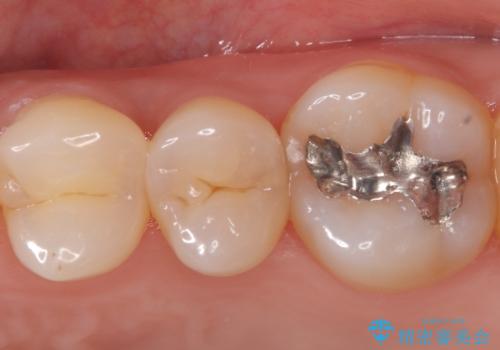

セラミッククラウンによる奥歯の修復

担当医 河口智英